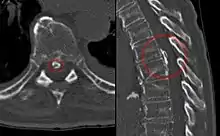

Imaging

Magnetic resonance imaging (MRI) is the preferred modality for the evaluation of back pain and visualization of bone, soft tissue, nerves and ligaments. X-rays are a less costly initial option offered to patients with a low clinical suspicion of infection or malignancy, and they are combined with laboratory studies for interpretation.

Imaging is not needed for the majority of patients with back pain. In cases of acute back pain, MRI is recommended for those with major risk factors or clinical suspicion of cancer, spinal infection or severe progressive neurological deficits.[37] For patients with subacute to chronic back pain, MRI is recommended if minor risk factors exist for cancer, ankylosing spondylitis or vertebral compression fracture, or if significant trauma or symptomatic spinal stenosis is present.[37]